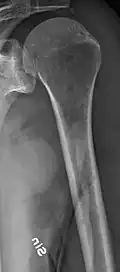

The diagnostic examination of a person with suspected multiple myeloma typically includes a skeletal survey. This is a series of X-rays of the skull, axial skeleton, and proximal long bones. Myeloma activity sometimes appears as "lytic lesions" (with local disappearance of normal bone due to resorption) or as "punched-out lesions" on the skull X-ray ("raindrop skull"). Lesions may also be sclerotic, which is seen as radiodense.[76] Overall, the radiodensity of myeloma is between −30 and 120 Hounsfield units (HU).[77] Magnetic resonance imaging is more sensitive than simple X-rays in the detection of lytic lesions. An MRI may supersede a skeletal survey, especially when vertebral disease is suspected. Occasionally, a CT scan is performed to measure the size of soft-tissue plasmacytomas. Nuclear Medicine Bone scans are typically not of any additional value in the workup of people with myeloma (no new bone formation; lytic lesions not well visualized on nuclear bone scan).

Multiple myeloma in the upper arm -

Femur with multiple myeloma lesions -